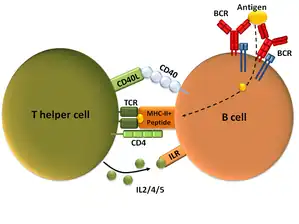

Lo característico de la patogenia del LES es la respuesta inmune dirigida contra los antígenos nucleares endógenos. Los autoantígenos liberados por células apoptóticas son presentados por las células dendríticas a los linfocitos T iniciando su activación. Estos linfocitos interactúan mediante citocinas como la interleucina 10 e interleucina 23 y mediante moléculas de superficie como el CD40L y el CTLA-4, con los linfocitos B para que éstos produzcan los anticuerpos contra estos componentes propios (por lo tanto se producen autoanticuerpos). También existe un mecanismo de producción de autoanticuerpos por los linfocitos B, no mediada por linfocitos T, a través de señales de los receptores BCR (propios de los linfocitos B) y los receptores de tipo Toll o TLRs.[8]

- Células B y T: en el LES se produce un aumento notable del número de células circulantes secretoras de inmunoglobulinas —hasta 50 veces—, junto con una activación selectiva de las células B, dirigidas contra un número determinado de antígenos.[46] Las células T son importantes en la activación de las células B y en la posterior producción de autoanticuerpos. Aunque en el LES el número total de células T está disminuido, se ha observado en estos pacientes la presencia de células T hiperactivas específicas para autoantígenos.[46] También se han descrito múltiples anomalías de señalización, tanto en los linfocitos T como en los B, incluyendo hiperactividad e hiperreactividad celular.[21][47] La hiperreacción de las células T y B se traduce en una mayor expresión de determinadas moléculas, como HLA-D y CD40L, lo que demuestra que las células son activadas fácilmente por los antígenos que inducen las primeras señales activadoras y las moléculas que estimulan la activación celular completa a través de la segunda señal. El resultado final de estas anormalidades es la producción sostenida de autoanticuerpos patógenos y la formación de inmunocomplejos que se adhieren a ciertos tejidos.[48]

- Autoanticuerpos e inmunocomplejos: los mediadores del LES son los autoanticuerpos y los inmunocomplejos que se forman con los antígenos. Los autoanticuerpos pueden estar presentes durante años antes de que aparezcan los primeros síntomas de la enfermedad.[51] Los autoantígenos que son reconocidos son presentados primariamente en la superficie de las células, particularmente por células activadas o bajo apoptosis, en las que los antígenos celulares han emigrado a la superficie celular, donde pueden ser reconocidas por el sistema inmune.[52] La fagocitosis y eliminación de los inmunocomplejos, de las células apoptóticas y de los restos derivados de las células necróticas son defectuosos en el LES, permitiendo la presencia de los antígenos y los inmunocomplejos durante períodos prolongados, haciendo que el daño en los tejidos vaya acumulándose hasta la aparición de la enfermedad clínica. Las células plasmáticas/células B que producen los autoanticuerpos están persistentemente activadas por el factor activador de células B (B lymphocyte stimulator o BLyS) y por las células T helper activadas, produciendo citoquinas como la IL-6 y IL-10.[21] También fallan en el LES los mecanismos de atenuación de estas funciones de las células T y B, incluyendo la generación de varios tipos de células T reguladoras y citolíticas y de sistemas atenuadores humorales idiotípicos.[48] Todos estos múltiples defectos originan una cascada de acontecimientos que comienzan con la anormal muerte celular y acaba en la célula B autoreactiva activada, proliferando y diferenciándose en células productoras de un exceso de autoanticuerpos frente a muchos antígenos nucleares. Además, y para complicar más la ya mala situación, se produce una activación del sistema inmune innato, con liberación de IL-1, TNF alfa, interferones, BLys y APRIL promoviendo la inflamación, además de la supervivencia de las células B autoreactivas. El resultado final es la producción de más anticuerpos antinucleares específicos, que pueden preceder a la manifestaciones clínicas durante años.[21]